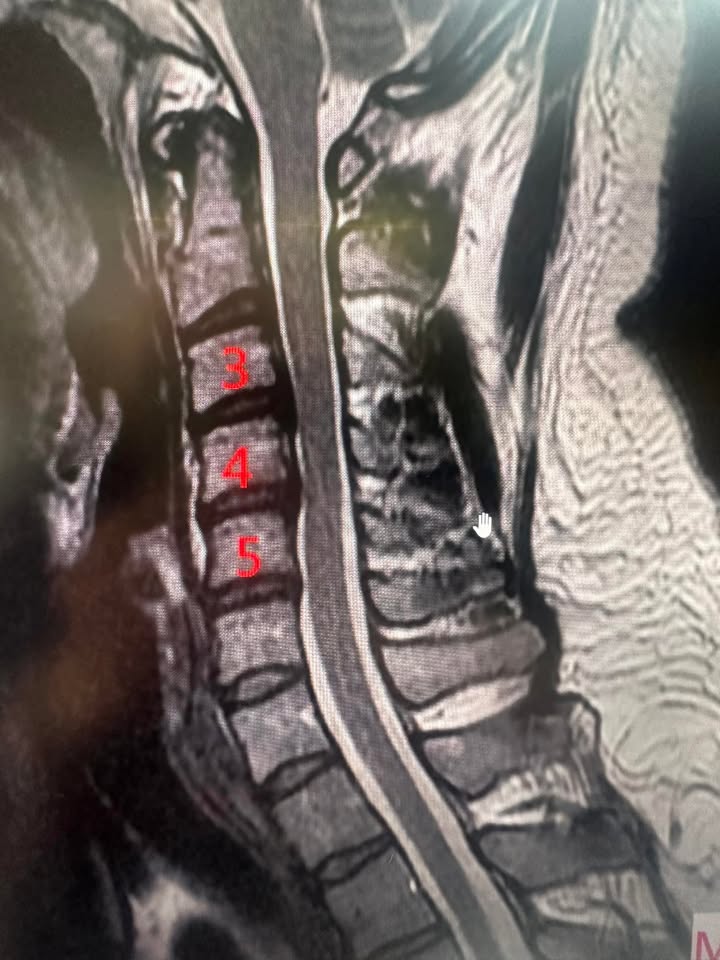

Cervical Spine Treatment Cases 精彩回顧 椎間盤突出合併骨裂及梨狀肌症候群 2023.11.08 2023.11.08 2023.11.11 神經根型頸椎病醫案 2023.11.15 2023.11.15 七周治療後成功逆轉 2023.11.16 腰椎滑脫醫案 2023.11.18 2023.11.20 2023.11.21 頸椎變形合併神經根型頸椎病醫案 2023.11.21 落診後出現嚴重的手麻 2023.11.22 2023.11.22 椎管狹窄合併突出醫案 2023.11.24 狹窄合併梨狀肌醫案 2023.11.25 頸椎變形合併神經根型醫案 2023.11.25 ← 上一頁 15 16 17 18 19 下一頁 →